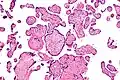

| Micrograph of villitis of unknown etiology. H&E stain. | |

Histomorphologically, VUE is characterized by a lymphocytic infiltrate of the chorionic villi without a demonstrable cause. Plasma cells should be absent; the presence of plasma cells suggests an infective etiology, e.g. CMV infection.